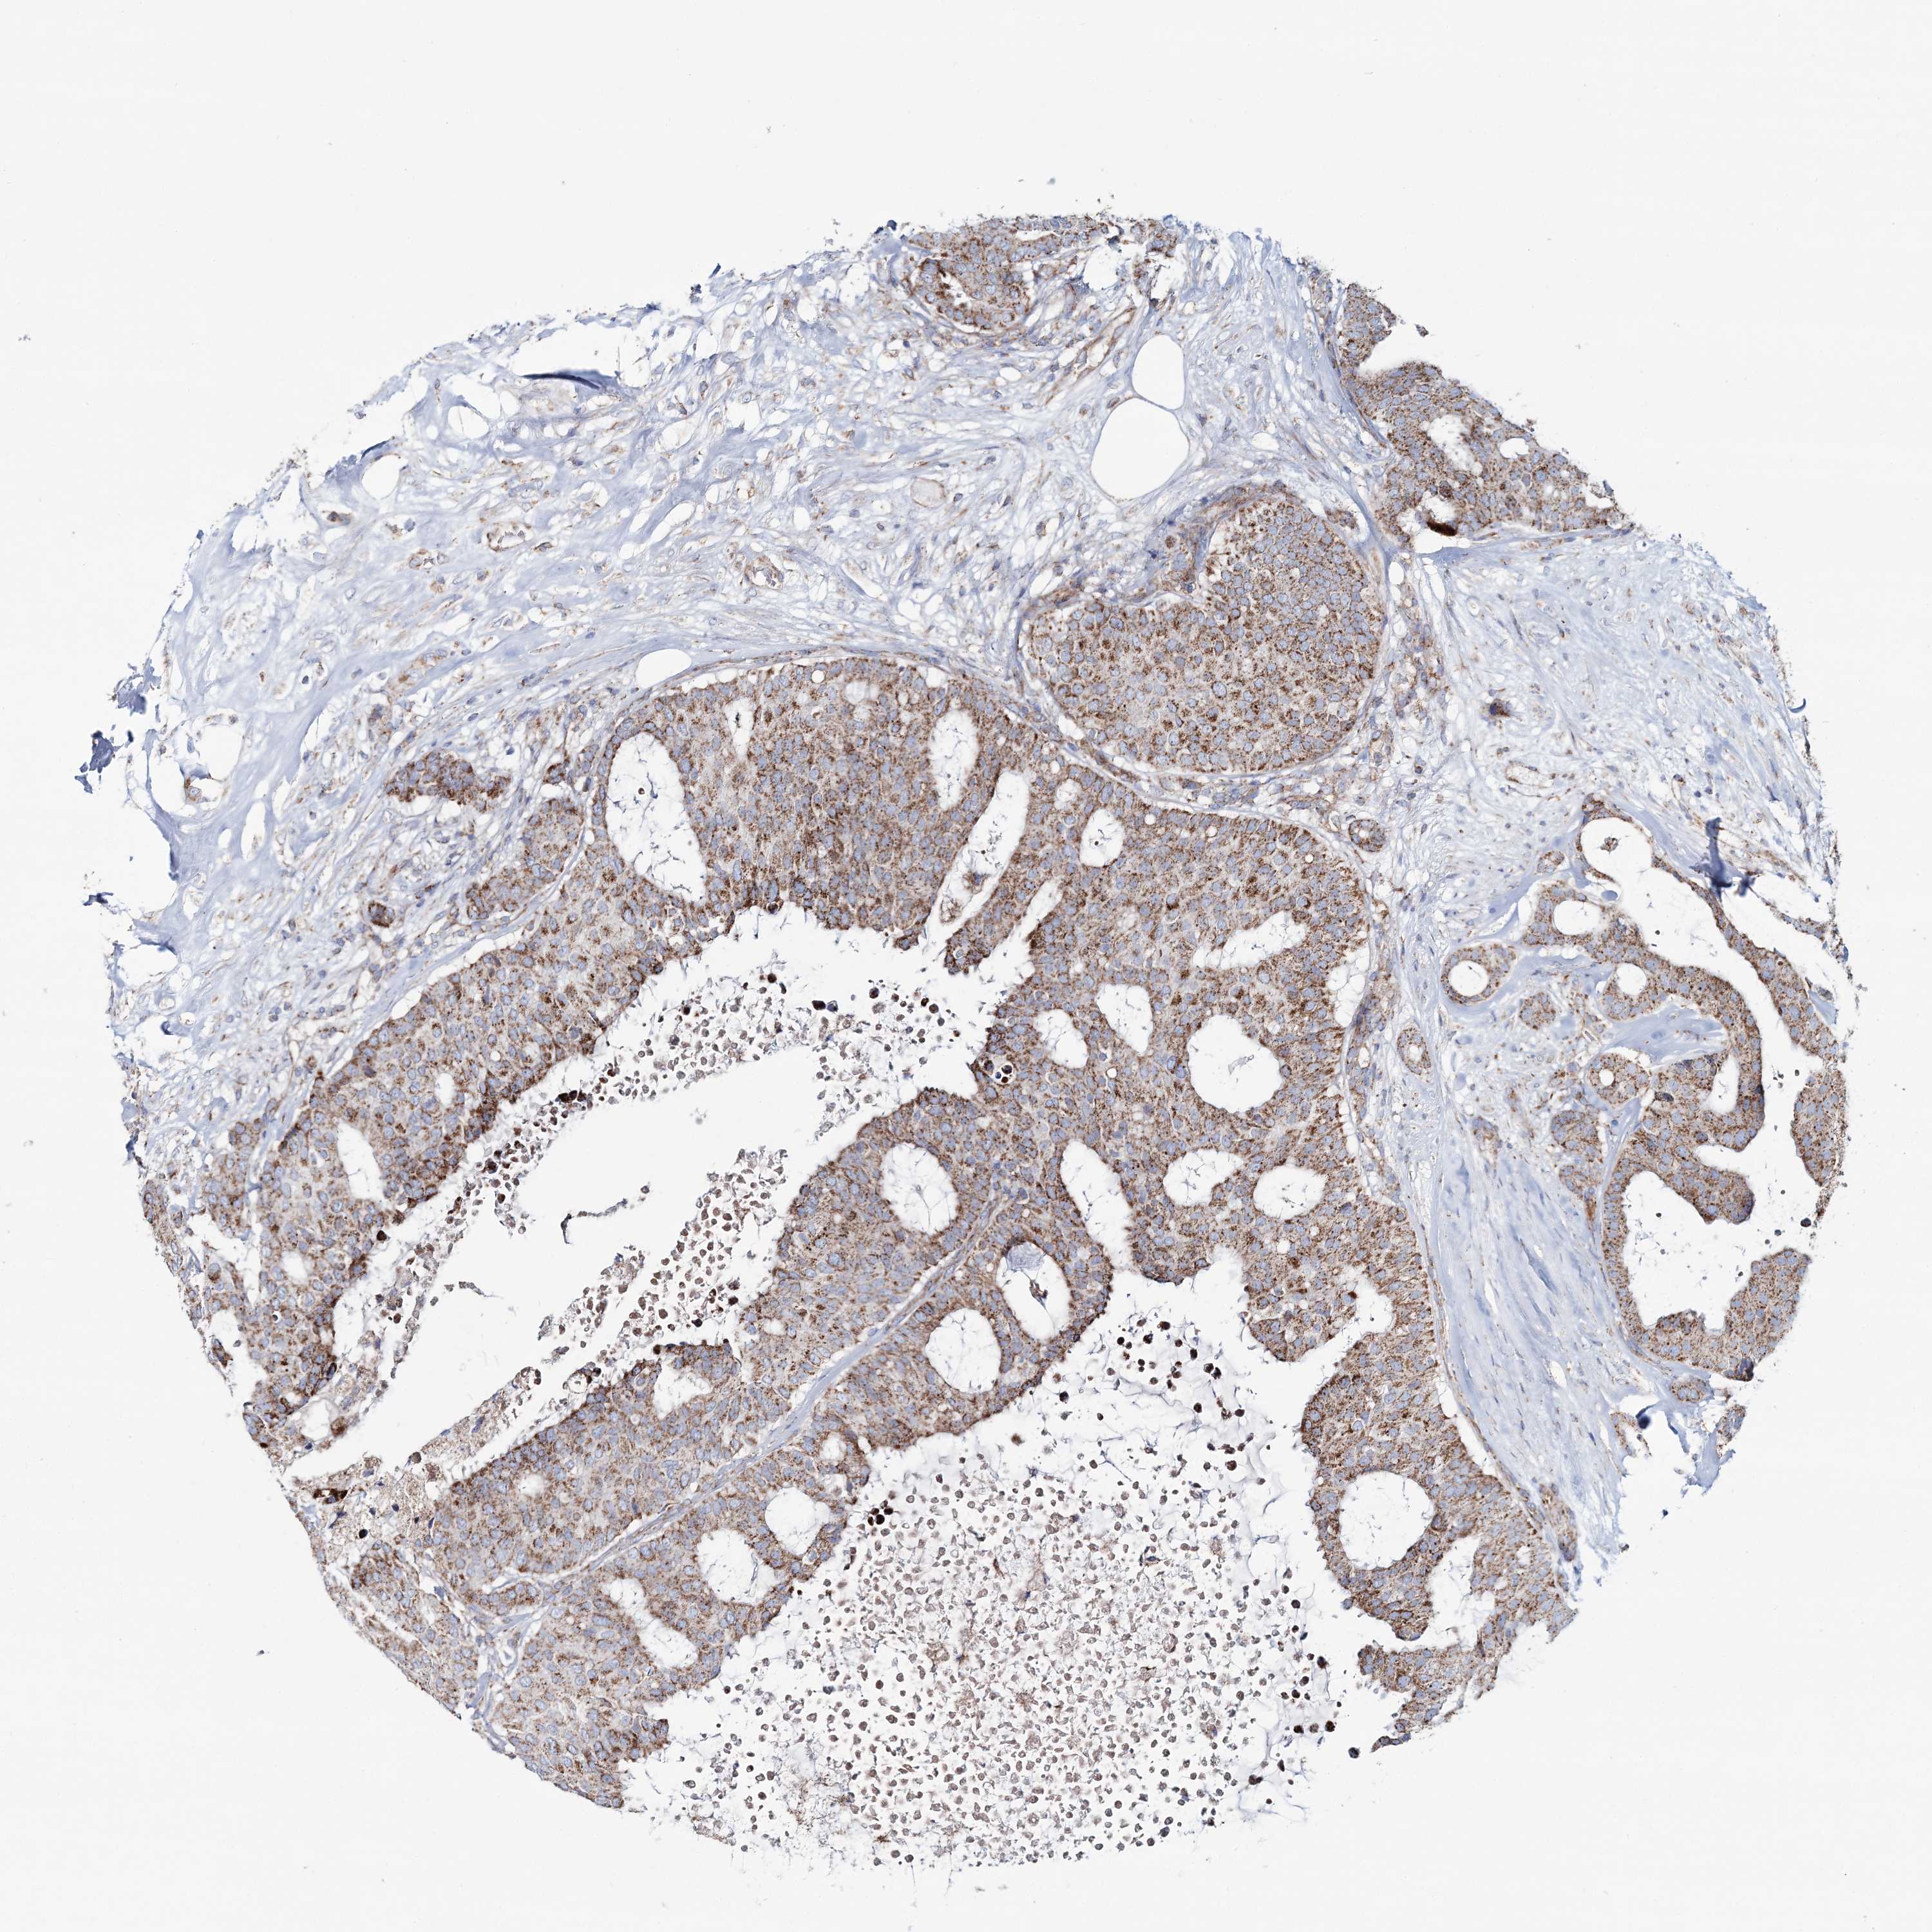

CANCER BREAST CANCER Show tissue menu

BRCA TCGA BRCA VALIDATION PROTEIN EXPRESSION

ANTIBODIES

AND

VALIDATION